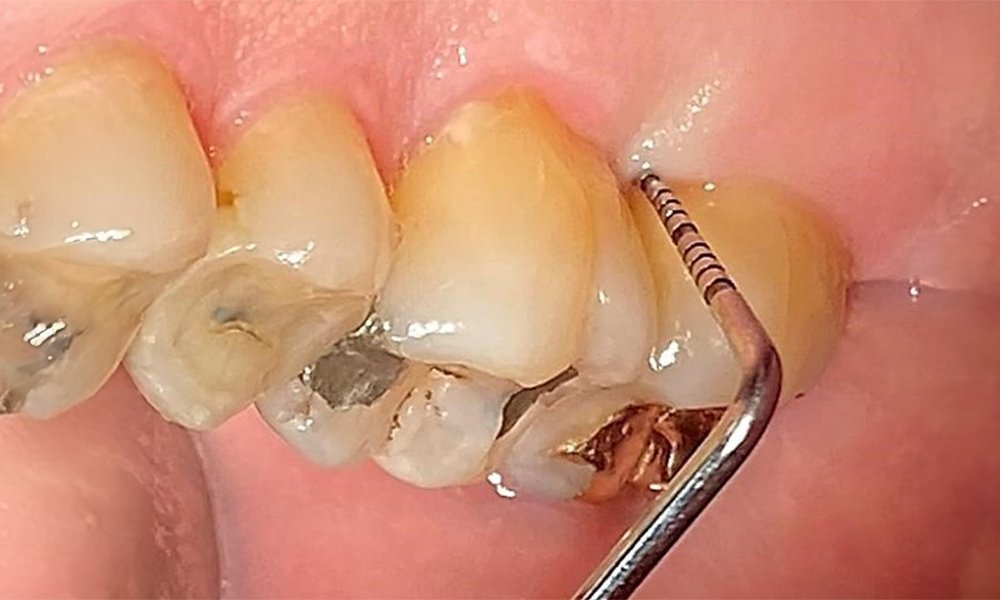

Probing to document the findings in tooth 27 mesiopalatal.

Fig. 8: Probing to document the findings in tooth 27 mesiopalatal. © Dr R. Krapf

The documentation of periodontal findings, including pocket depth probing and bleeding status, is mandatory during each dental appointment due to the presence of periodontitis (Fig. 8). This will record the individual therapeutic needs and facilitate a rapid response to any progression of the pre-existing periodontitis.

Detailed periodontal findings, including the documentation of pocket depths, bleeding on probing, recessions, furcation involvement and degree of loosening, must be examined annually.